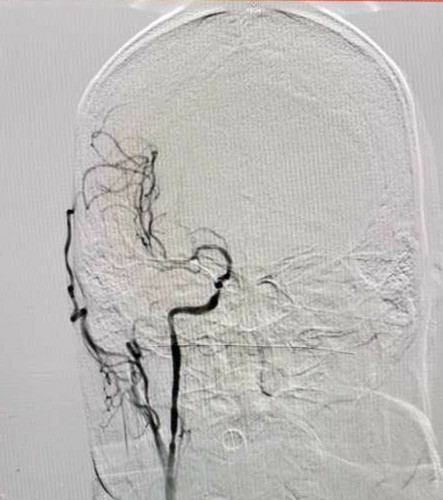

病例二:慢性颈动脉闭塞开通手术

反复左侧肢体无力,造影显示右侧颈动脉慢性闭塞。(下图)